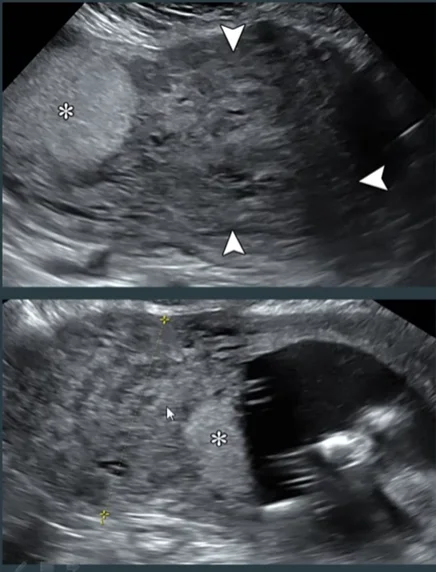

• U xơ tử cung trong thai kỳ (Myoma in Pregnancy)